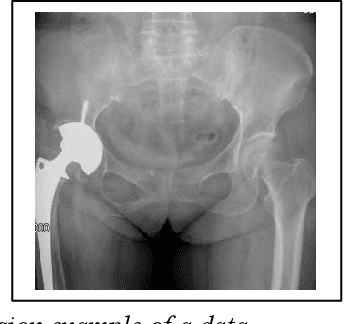

Abstract:Prosthetic Joint Infection (PJI) is a prevalent and severe complication characterized by high diagnostic challenges. Currently, a unified diagnostic standard incorporating both computed tomography (CT) images and numerical text data for PJI remains unestablished, owing to the substantial noise in CT images and the disparity in data volume between CT images and text data. This study introduces a diagnostic method, HGT, based on deep learning and multimodal techniques. It effectively merges features from CT scan images and patients' numerical text data via a Unidirectional Selective Attention (USA) mechanism and a graph convolutional network (GCN)-based feature fusion network. We evaluated the proposed method on a custom-built multimodal PJI dataset, assessing its performance through ablation experiments and interpretability evaluations. Our method achieved an accuracy (ACC) of 91.4\% and an area under the curve (AUC) of 95.9\%, outperforming recent multimodal approaches by 2.9\% in ACC and 2.2\% in AUC, with a parameter count of only 68M. Notably, the interpretability results highlighted our model's strong focus and localization capabilities at lesion sites. This proposed method could provide clinicians with additional diagnostic tools to enhance accuracy and efficiency in clinical practice.

Abstract:Postoperative infection diagnosis is a common and serious complication that generally poses a high diagnostic challenge. This study focuses on PJI, a type of postoperative infection. X-ray examination is an imaging examination for suspected PJI patients that can evaluate joint prostheses and adjacent tissues, and detect the cause of pain. Laboratory examination data has high sensitivity and specificity and has significant potential in PJI diagnosis. In this study, we proposed a self-supervised masked autoencoder pre-training strategy and a multimodal fusion diagnostic network MED-NVC, which effectively implements the interaction between two modal features through the feature fusion network of CrossAttention. We tested our proposed method on our collected PJI dataset and evaluated its performance and feasibility through comparison and ablation experiments. The results showed that our method achieved an ACC of 94.71% and an AUC of 98.22%, which is better than the latest method and also reduces the number of parameters. Our proposed method has the potential to provide clinicians with a powerful tool for enhancing accuracy and efficiency.